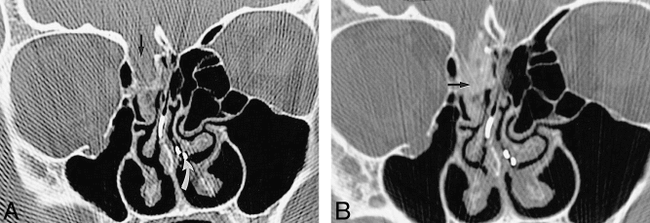

Patient with a bone defect revealed by CT and a leak evident by CT cisternography but not by radionuclide cisternography.

A, Coronal CT scan of the face shows a large defect (straight arrow) in the right cribriform plate with adjacent mucosal thickening. Nasal pledgets can be seen within the nasal cavity (curved arrow).

B, Coronal CT cisternogram of the same region shows accumulation of contrast medium at the defect and extending into the ethmoidal sinus (arrow). The results of radionuclide cisternography and nasal pledgets were normal. There was no surgical confirmation.